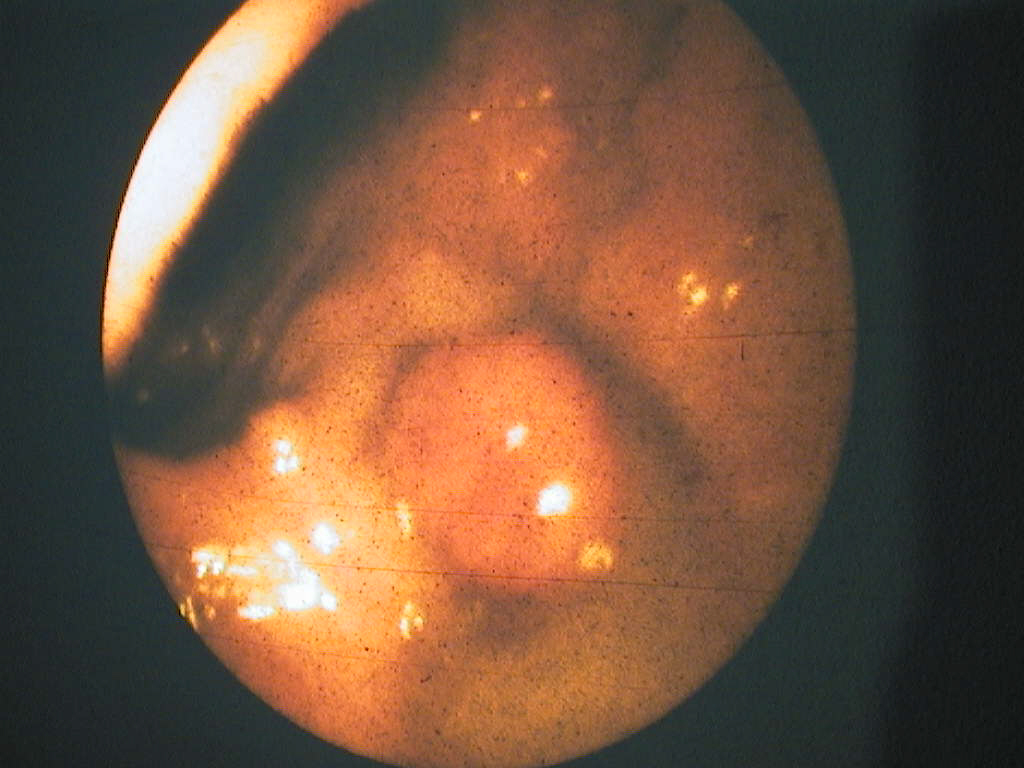

Duodenoscopy: periampullary regio`s tumour.

Duodenoscopie: tumoră a regiunii periampulare.

Sigmoidoscopy: multiple poliposis tumours.

Sigmoidoscopie: tumori polipoide multiple.